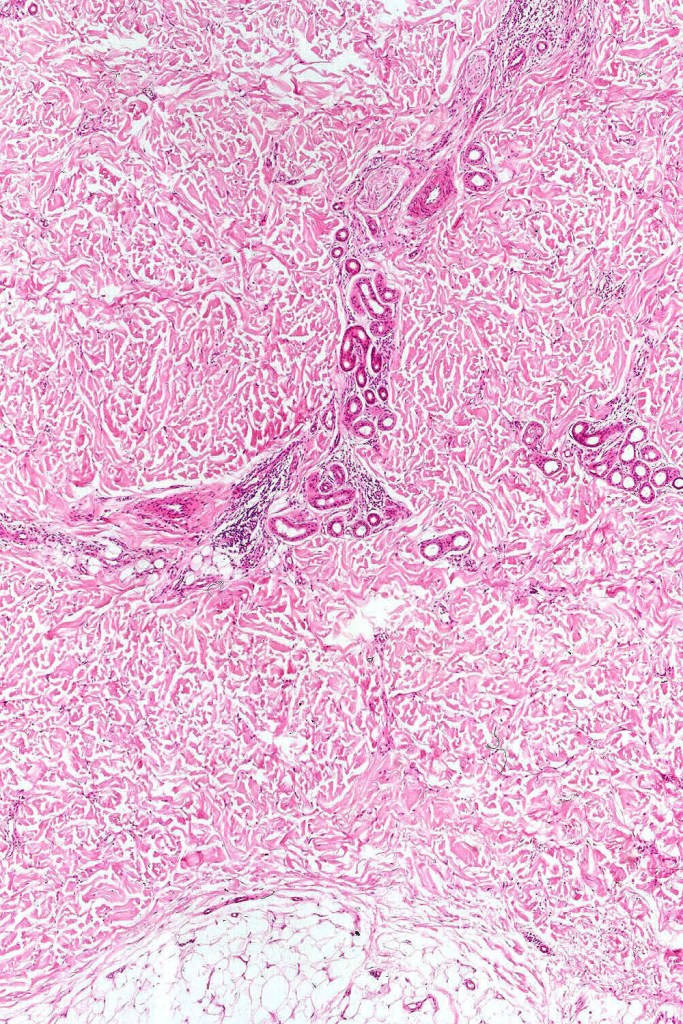

Histologically, it is characterized by a dense population of spindled, dendritic melnanocytes & melanophages with variable fibrosis. It may sometimes represent a component of a combined nevus. Mitotic activity is not usually present and pleomorphism is absent (see atypical blue nevus below). Involvement of the arrector pili muscle is not uncommon.

•Most characteristic is the dumbbell silhouette although a plague morphology may also be encountered

•Admixture of spindle cells, pigmented bipolar or dendritic cells & melanophages

•An alveolar pattern is characteristic particularly with clear cell nodules

•Stromal fibrosis, myxoid change, vascular hyalinization with cyst formation are often seen